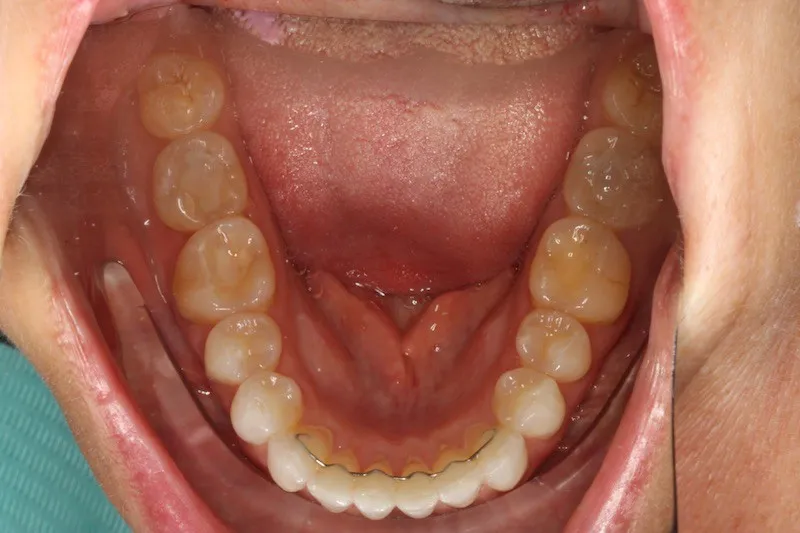

Case Study #1: 20 months of Invisalign for better alignment and bite.

Case Study #2: Invisalign for Crowding and To Widen Arches, 22 months

Case Study #3: Invisalign for Teeth Crowding

Case Study #4: Invisalign for Rotations/Crowding

Case Study #5: Short Course Invisalign for 8 Months

Case Study #6: 24-Month Invisalign Treatment

Case Study #7: 20 months of Invisalign to correct front crossbites. A crossbite is when one or more top teeth sit behind the bottom teeth

Case Study #8: Invisalign for 21 months to fix an anterior open bite

Case Study #9: 28 months of Invisalign for better alignment and bite.